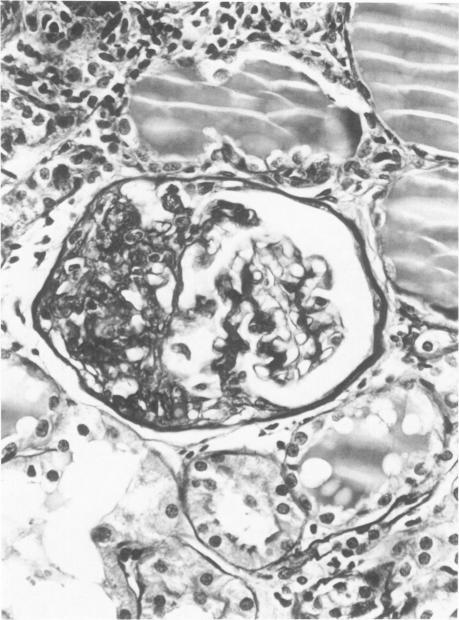

Advances in our understanding of the mechanisms of proteinuria in humans have depended on a variety of animal models. Most of these have been partially satisfactory because they require pretreatment of the animal with chemicals or toxins or they depend on an aging-related glomerular protein leakiness. The strain in this study was obtained by Koletsky after selective inbreeding of the offspring from a hypertensive Kyoto-Wistar and a normotensive Sprague-Dawley rat. The affected animals appear in 25% of the litters, indicating an autosomal recessive gene, and present with a spontaneous and progressive nephrotic syndrome detected as early as 3-5 weeks and associated with obesity, hypertension, hypoalbuminemia, hypercholesterolemia, and hyperlipidemia. Preliminary morphologic and immunofluorescence studies of their kidneys show progressive glomerular segmental sclerotic lesions and prominent mesangial deposition of IgM, a picture which resembles a steroid-resistant form of idiopathic nephrotic syndrome in humans, namely, focal glomerular sclerosis.

我们对人类蛋白尿机制认识的进展依赖于多种动物模型。其中大多数只是部分令人满意,因为它们需要用化学物质或毒素对动物进行预处理,或者依赖于与衰老相关的肾小球蛋白渗漏。本研究中的品系是科莱茨基通过对一只高血压京都-威斯塔大鼠和一只正常血压的斯普拉格-道利大鼠的后代进行选择性近亲繁殖获得的。受影响的动物出现在25%的窝中,表明是常染色体隐性基因,早在3 - 5周时就出现自发进行性肾病综合征,并伴有肥胖、高血压、低白蛋白血症、高胆固醇血症和高脂血症。对其肾脏进行的初步形态学和免疫荧光研究显示,肾小球逐渐出现节段性硬化病变,IgM在系膜区显著沉积,这一情况类似于人类类固醇抵抗型特发性肾病综合征,即局灶性肾小球硬化。